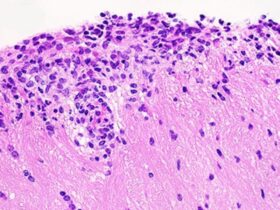

Cicinelli E, De Ziegler D, Nicoletti R, Colafiglio G, Saliani N, Resta L, et al. Chronic endometritis: correlation among hysteroscopic, histologic, and bacteriologic findings in a prospective trial with 2190 consecutive office hysteroscopies. Fertil Steril. 2008;89:677–84.

Song D, Li TC, Zhang Y, Feng X, Xia E, Huang X, et al. Correlation between hysteroscopy findings and chronic endometritis. Fertil Steril. 2019;111:772–9.

Kitaya K, Yasuo T. Immunohistochemical and clinicopathological characterization of chronic endometritis. Am J Reprod Immunol. 2011;66:410–5.